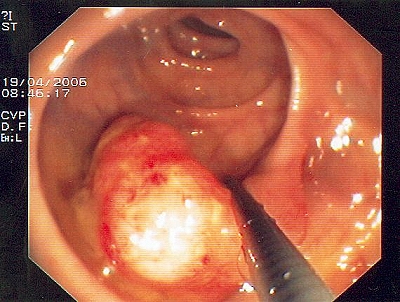

Gut sichtbarer Blutstrahl nach Abtragung eines Polypen

Sichere Blutstillung durch einen Metallclip